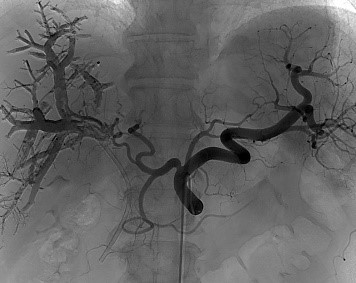

Програмне забезпечення 3D Roadmap

Флюороскопія в реальному масштабі часу накладається на об’ємні 3D зображення, що були отримані під час 3D ангіографії. При русі столу під час роботи в режимі 3D Roadmap автоматично відбувається співставлення зображення 3D та флюороскопічного. Всі рухи системи пов’язані з накладанням 3D об’єму та скопічних зображень, включаючи зміну кута нахилу С-арки, SID, розміру поля огляду, висоти позиціонування столу. Можливим є зсув попіксельно вручну для більш точного співставлення об’єму та флюоро.